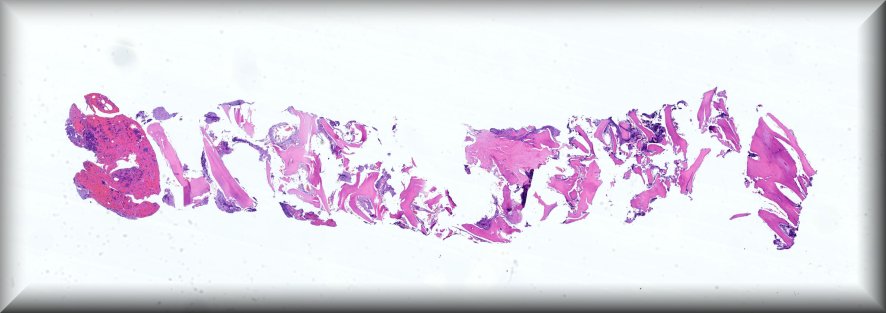

Caso 1.- María José Naharro Gascón, Julieta Romina Arbat, Elizabeth Burch Nchama, Amparo Taverner Lino, Encarna Marti Ibor, Maria Luisa Pérez Ebri.

Hospital Doctor Peset de Valencia.

Varón de 44 años que consulta por múltiples adenopatías en regiones inguinal y pélvica, que en el estudio PET-TC muestra captación e hipermetabolismo en esternón y escápula en relación a posible infiltración de médula ósea. Además, presenta en rodilla derecha a nivel cutáneo una lesión nodular indurada y violácea, de 1 cm de tamaño. No presenta afectación del estado general ni síntomas B. En el estudio por sospecha de neoplasia hematológica se realiza biopsia de médula ósea.